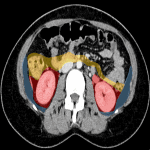

Các khoang sau phúc mạc (Retroperitoneal spaces): Gồm 3 khoang ở mỗi bên cơ thể và một khoang ở giữa: Khoang cạnh thận trước; Khoang cạnh thận sau; Khoang quanh thận; Khoang quanh mạch máu…